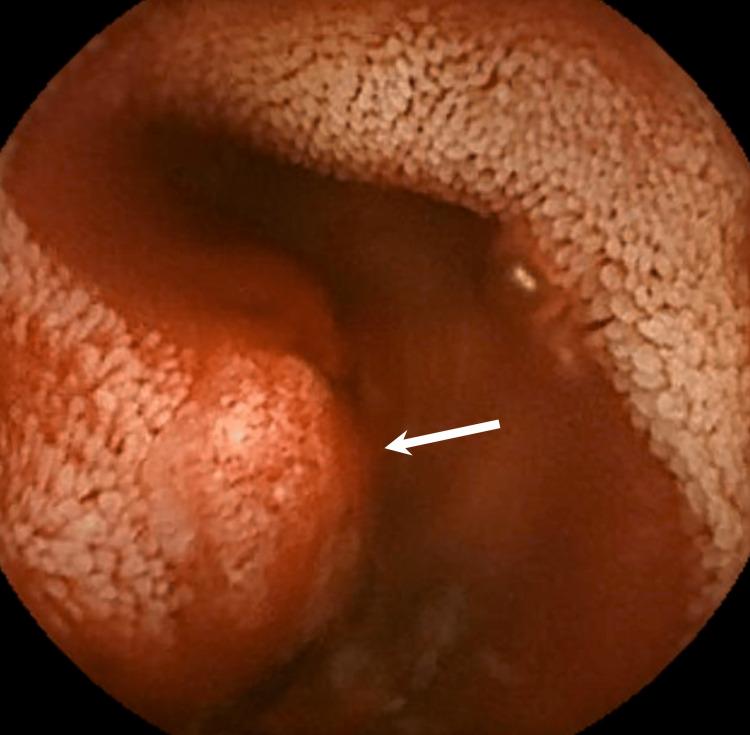

Small bowel arteriovenous malformation (AVM) is a rare vascular lesion, which should be considered in patients presenting with gastrointestinal bleeding, as it is a high-flow arterial lesion that can cause life-threatening bleeding. Although a primary endoscopic examination is performed in cases of suspected small bowel bleeding, the diagnosis of the causal lesion is sometimes difficult. We are presenting a case of small bowel AVM that could not be diagnosed endoscopically but was successfully detected using multiphase CT images with an appropriate protocol. The AVM diagnosis was confirmed using digital subtraction angiography. An endovascular coil is placed in the draining vein as a surgical resection marker. The AVM was resected successfully without any complications.

小肠动静脉畸形(AVM)是一种罕见的血管病变,对于出现胃肠道出血的患者应考虑到这种病变,因为它是一种高流量动脉病变,可导致危及生命的出血。尽管在疑似小肠出血的病例中会进行初步内镜检查,但有时很难诊断出病因性病变。我们现报告一例小肠AVM,内镜检查未能诊断出来,但通过采用适当方案的多期CT图像成功检测到了该病变。通过数字减影血管造影术确诊为AVM。在引流静脉中放置了一个血管内线圈作为手术切除标记物。成功切除了AVM,未出现任何并发症。